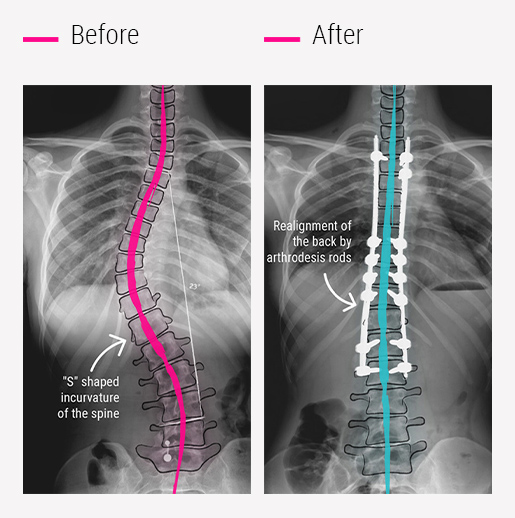

Scoliosis Surgery